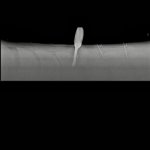

X-ray below- have circled the one which is very tight.

X-ray below- have circled the one which is very tight.